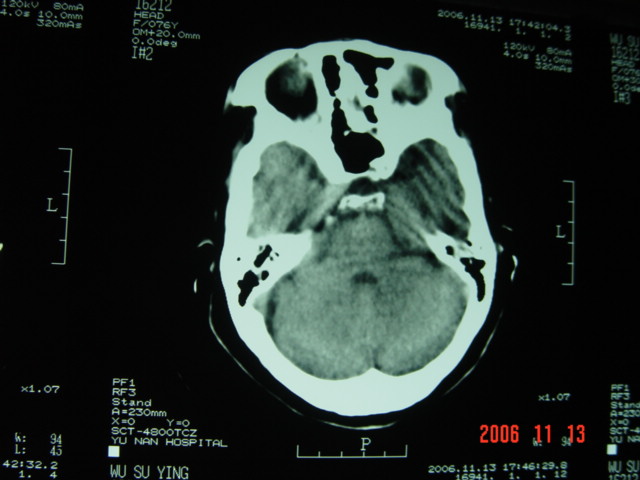

失语及右侧肢体无力3小时

左侧大脑半球与对侧相比较密度普遍密度降低,结合临床首先考虑是脑梗塞早期,必要时复查或mri。

左侧脑表面脑变窄,左外侧裂池受压变窄。

左侧大脑半球密度减低,左外侧裂消失。脑梗塞急性期

左侧侧裂池消失,脑沟变浅.典型的一侧大脑半球缺血改变.可以诊断:左侧大面积脑梗塞.

左侧大脑半球大片密度减低影,脑沟变浅,外侧裂变窄,中线结构无明显移位。左侧大面积脑梗塞,大脑中动脉堵塞所致,愈后不好呀!应早期溶栓啊。

典型的左侧大脑半球早期缺血性脑梗塞(符合大脑前动脉、中动脉、大脑后动脉供血区。)

典型的左侧大脑半球缺血性脑梗塞早期表现[左侧大脑半球皮质密度减低与脑白质密度一致(脑皮质征),左侧豆状核轮廓模糊,密度与脑白质一致(豆状核征),结合临床有失语及右侧肢体无力3小时]。